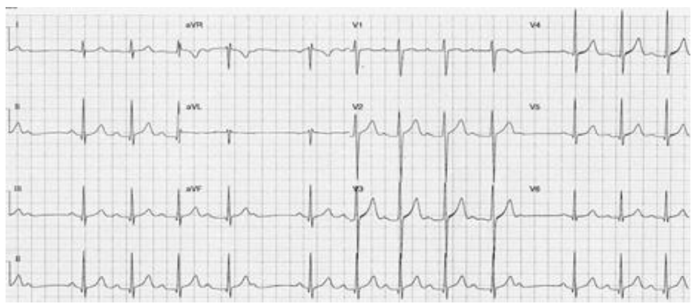

Mulher de 68 anos, com hipertensão e dislipidemia, foi atendida na emergência devido à dor torácica com 90 minutos de evolução. O

eletrocardiograma de admissão foi compatível com uma síndrome coronariana aguda com supradesnível de ST de parede inferior.

Encaminhada imediatamente à hemodinâmica e submetida à angioplastia com implante de stent no segmento proximal da coronária

direita com sucesso. Houve resolução da dor e do supradesnível do segmento ST, e não havia lesões residuais. Mantida dupla antiagregação

plaquetária, ao ser internada na unidade cardiointensiva seu eletrocardiograma revelou o traçado abaixo. No momento do registro a

paciente estava assintomática, com frequência cardíaca 70 bpm, pressão arterial 124x66 mmHg, e sem sinais de congestão pulmonar.